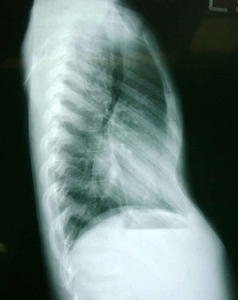

術前X光照片

漏斗胸為最常見的先天胸壁畸型,此漏斗胸由外表判斷,可小至放置一個網球而不會掉落地面,可大至兩乳之間皆凹陷,嚴重影響心肺功能。由於胸肋骨的畸型,而造成胸骨向脊椎方向凹陷,甚至最嚴重的畸型是胸骨與脊椎骨相當靠近,造成原先位在兩者之間的心臟被推向左邊,肺部的擴張空間變小,甚至會影響心肺功能,而被壓迫的心臟及肺部的位置及形狀,可由電腦斷層掃描明顯診斷之。